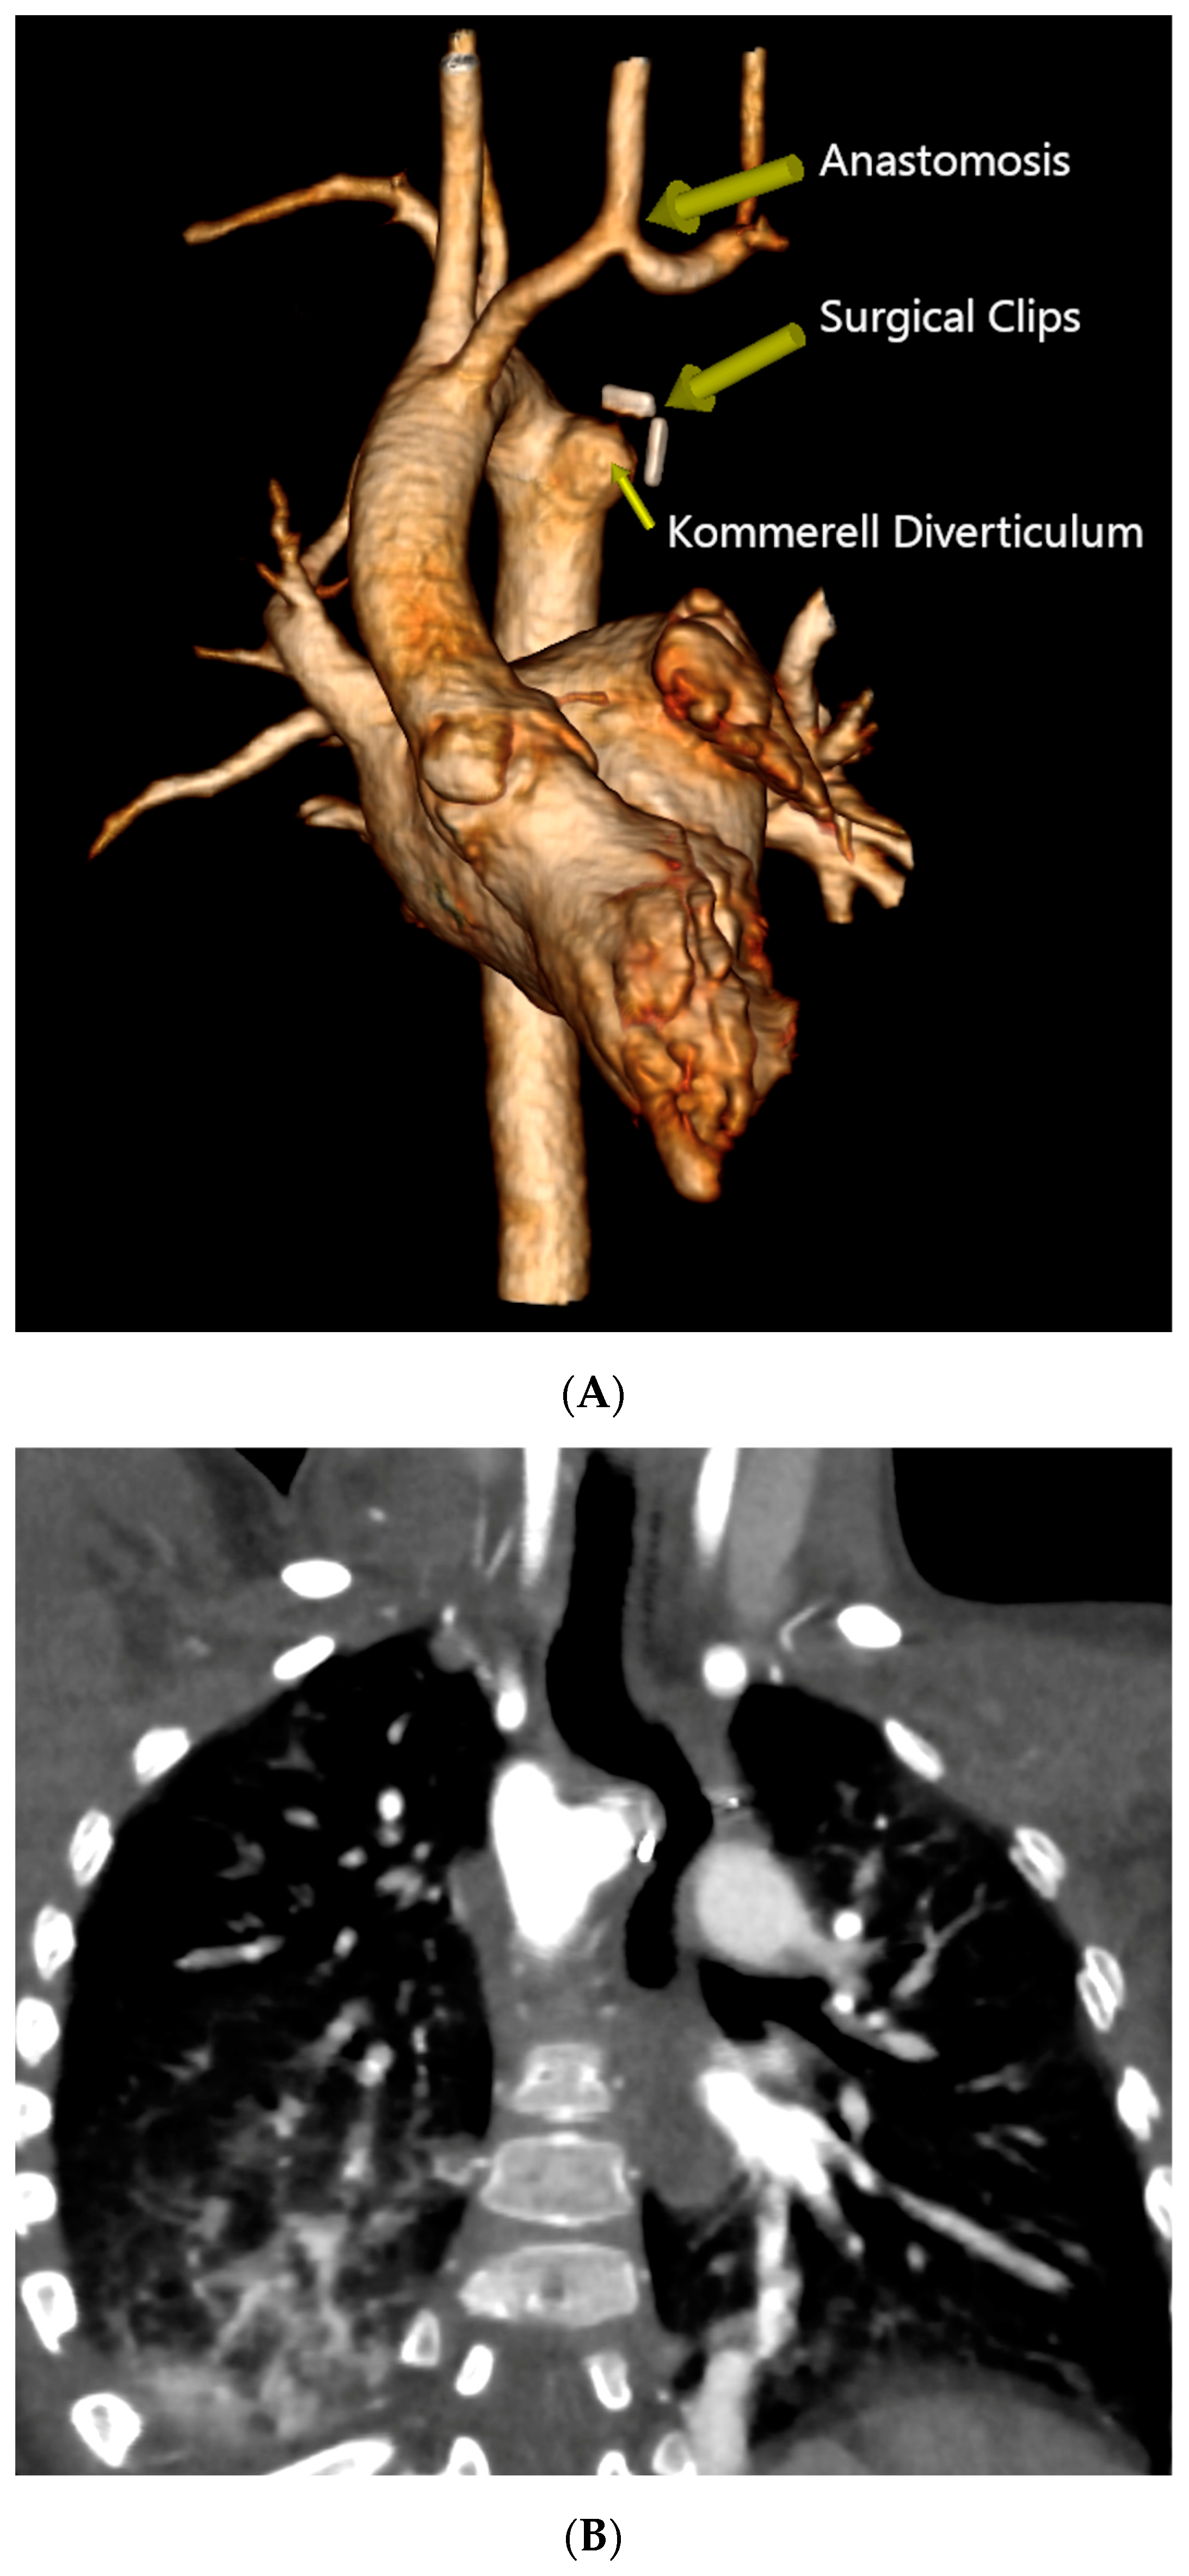

The patient was then placed on a gastrostomy tube and followed up until 14 months of age, showing persistent dysphagia and weighing 8.2 kg. Hence, the decision was made to perform a surgical repair of the vascular ring. Prior to the surgical incision, an endoscopic and EndoFLIPTM evaluation were conducted, demonstrating an esophageal narrowing at the level of the vascular ring and an abnormal increase in esophageal impedance, respectively. A limited left posterior thoracotomy was performed, allowing the visualization of a left-sided esophagus with a RAA originating from behind, and an aberrant LSA exiting from a KD. The LLA, which was observed compressing the esophagus, was divided. The KD was obliterated, with two purse-string sutures, and the aberrant LSA was dissected and divided from the aorta, then re-implanted into the left carotid artery (LCA) via an end-to-side anastomosis. Following the closure of the chest, another endoscopic evaluation and EndoFLIPTM assessment were performed, which evidenced an improvement in esophageal narrowing and impedance, respectively. The patient’s recovery was uneventful, and she was discharged on postoperative day 4. Follow-up visits demonstrated symptomatic improvement without postoperative complications, and she was meeting her growth milestones. A recent CTA performed 2 years post-procedure revealed a patent re-implanted LSA into the LCA and no tracheal deformities (Figure 3) (Supplementary Material Video S2–S4).

Figure 3.

Postoperative Computed Tomography Angiography. (A) Three-dimensional reconstruction showing the RAA status post KD plication and LSA re-implantation into the LCA, evidencing patency of the re-implanted artery and an outpouching of the KD’s remnant with a surgical clip at the distal end. (B) Coronal view demonstrating esophageal displacement without evident narrowing. (C) Coronal view evidencing no tracheal deformities.